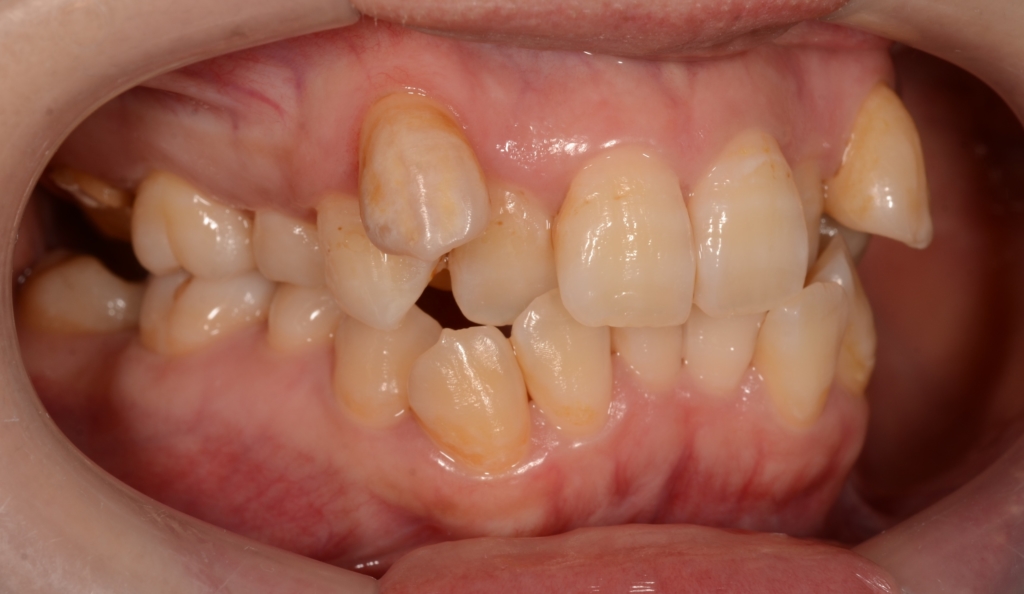

患者さんは、30代の女性(社会人)です。

「八重歯などのガタガタを治してきれいな歯並びになりたい!」

というのが一番の希望でした。

合わせて、口元が少しでも引っ込んで、お口を閉じる時にオトガイ辺りの「力」が抜けてしわが無くなればもっと嬉しい!とのことでした。

#1.顎と歯の不調和による叢生(重度)

#2.上顎前突(出っ歯)傾向

と診断しました。